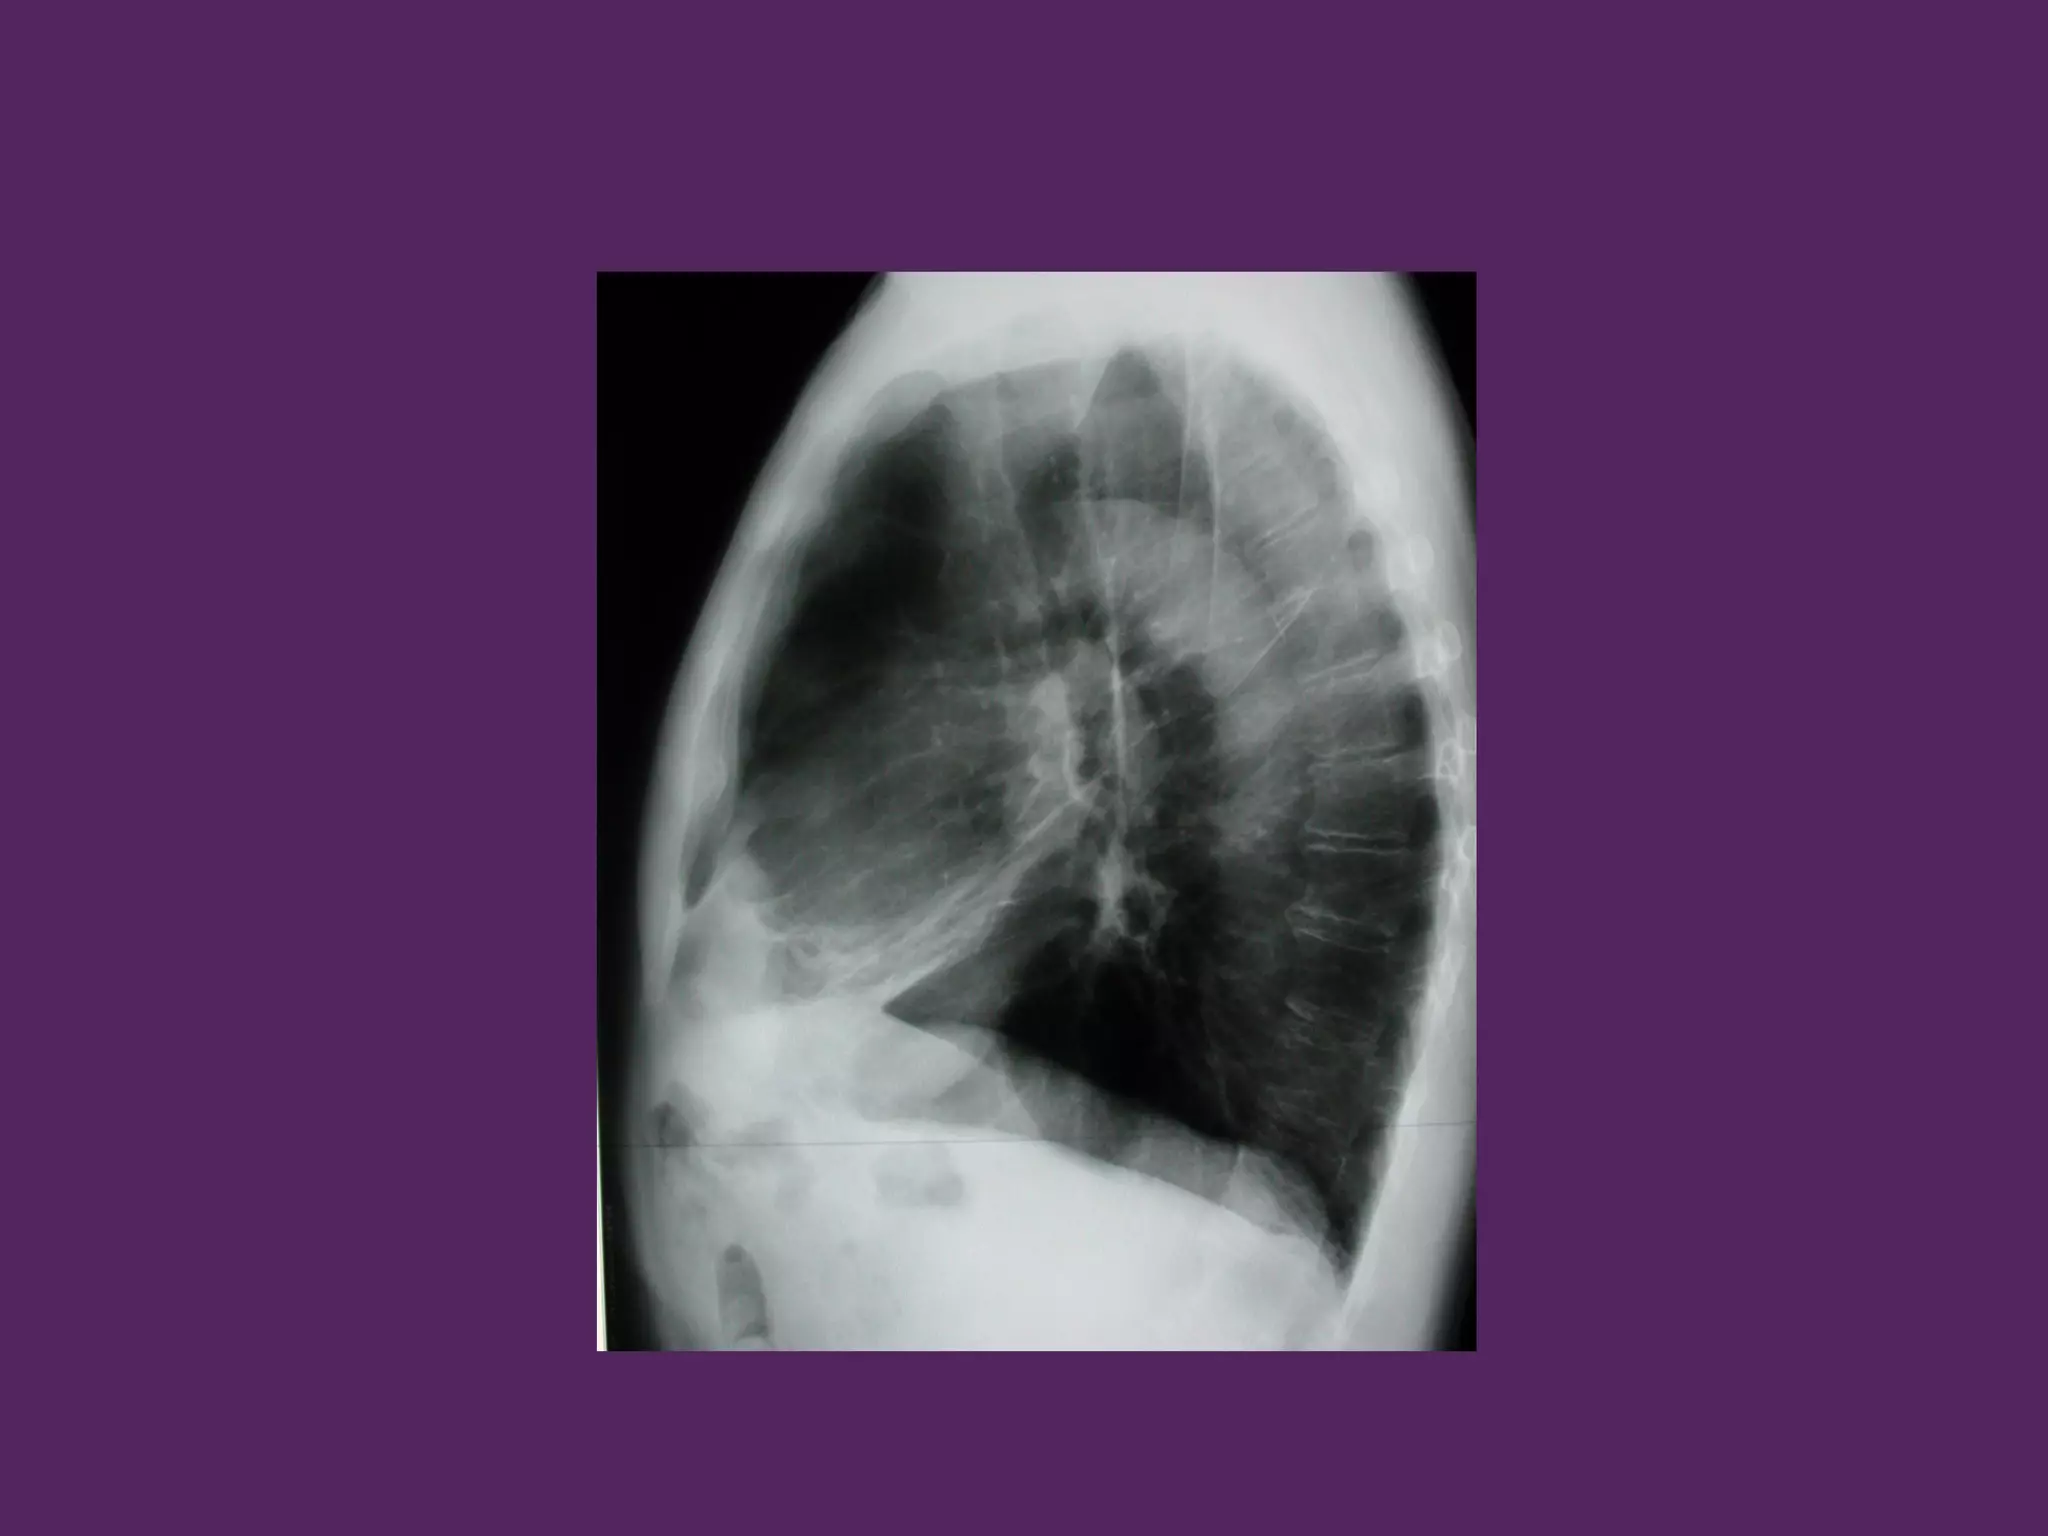

HÌNH ẢNH HỌC

- Căng dãn lồng ngực

- Tăng sáng phế trường

- Giảm số lượng mạch máu

HÌNH ẢNH HỌC -Căng dãn lồng ngực - Tăng sáng phế trường - Giảm số lượng mạch máu